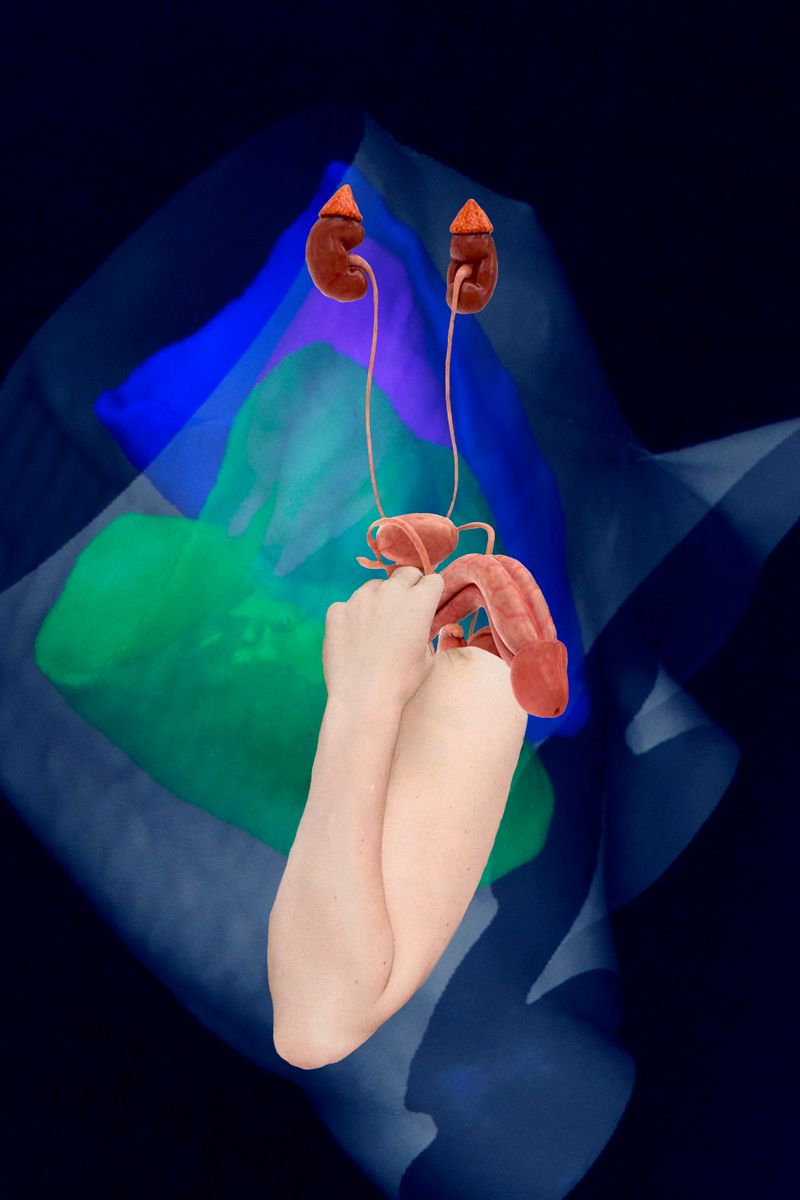

Due to health problems within my family including myself this work derives from a long- term engagement with the human body, its mal-functions and collateral mental issues.

Due to health problems within my family including myself this work derives from a long- term engagement with the human body, its mal-functions and collateral mental issues.

Since the topic being serious and threatening at times, the analysis within the terms of art began to shift from depressing states and strong depictions to more symbolic style of expression alleviating the whole issue.

Combining digital 3-D models of inner organs from the web with scanned cut-outs from magazines, different kind of free associations are made possible. The background consisting of CTs from my check-up enhances the issue of the fragility of our body.

Each image describes a mental state during this period of endurance.